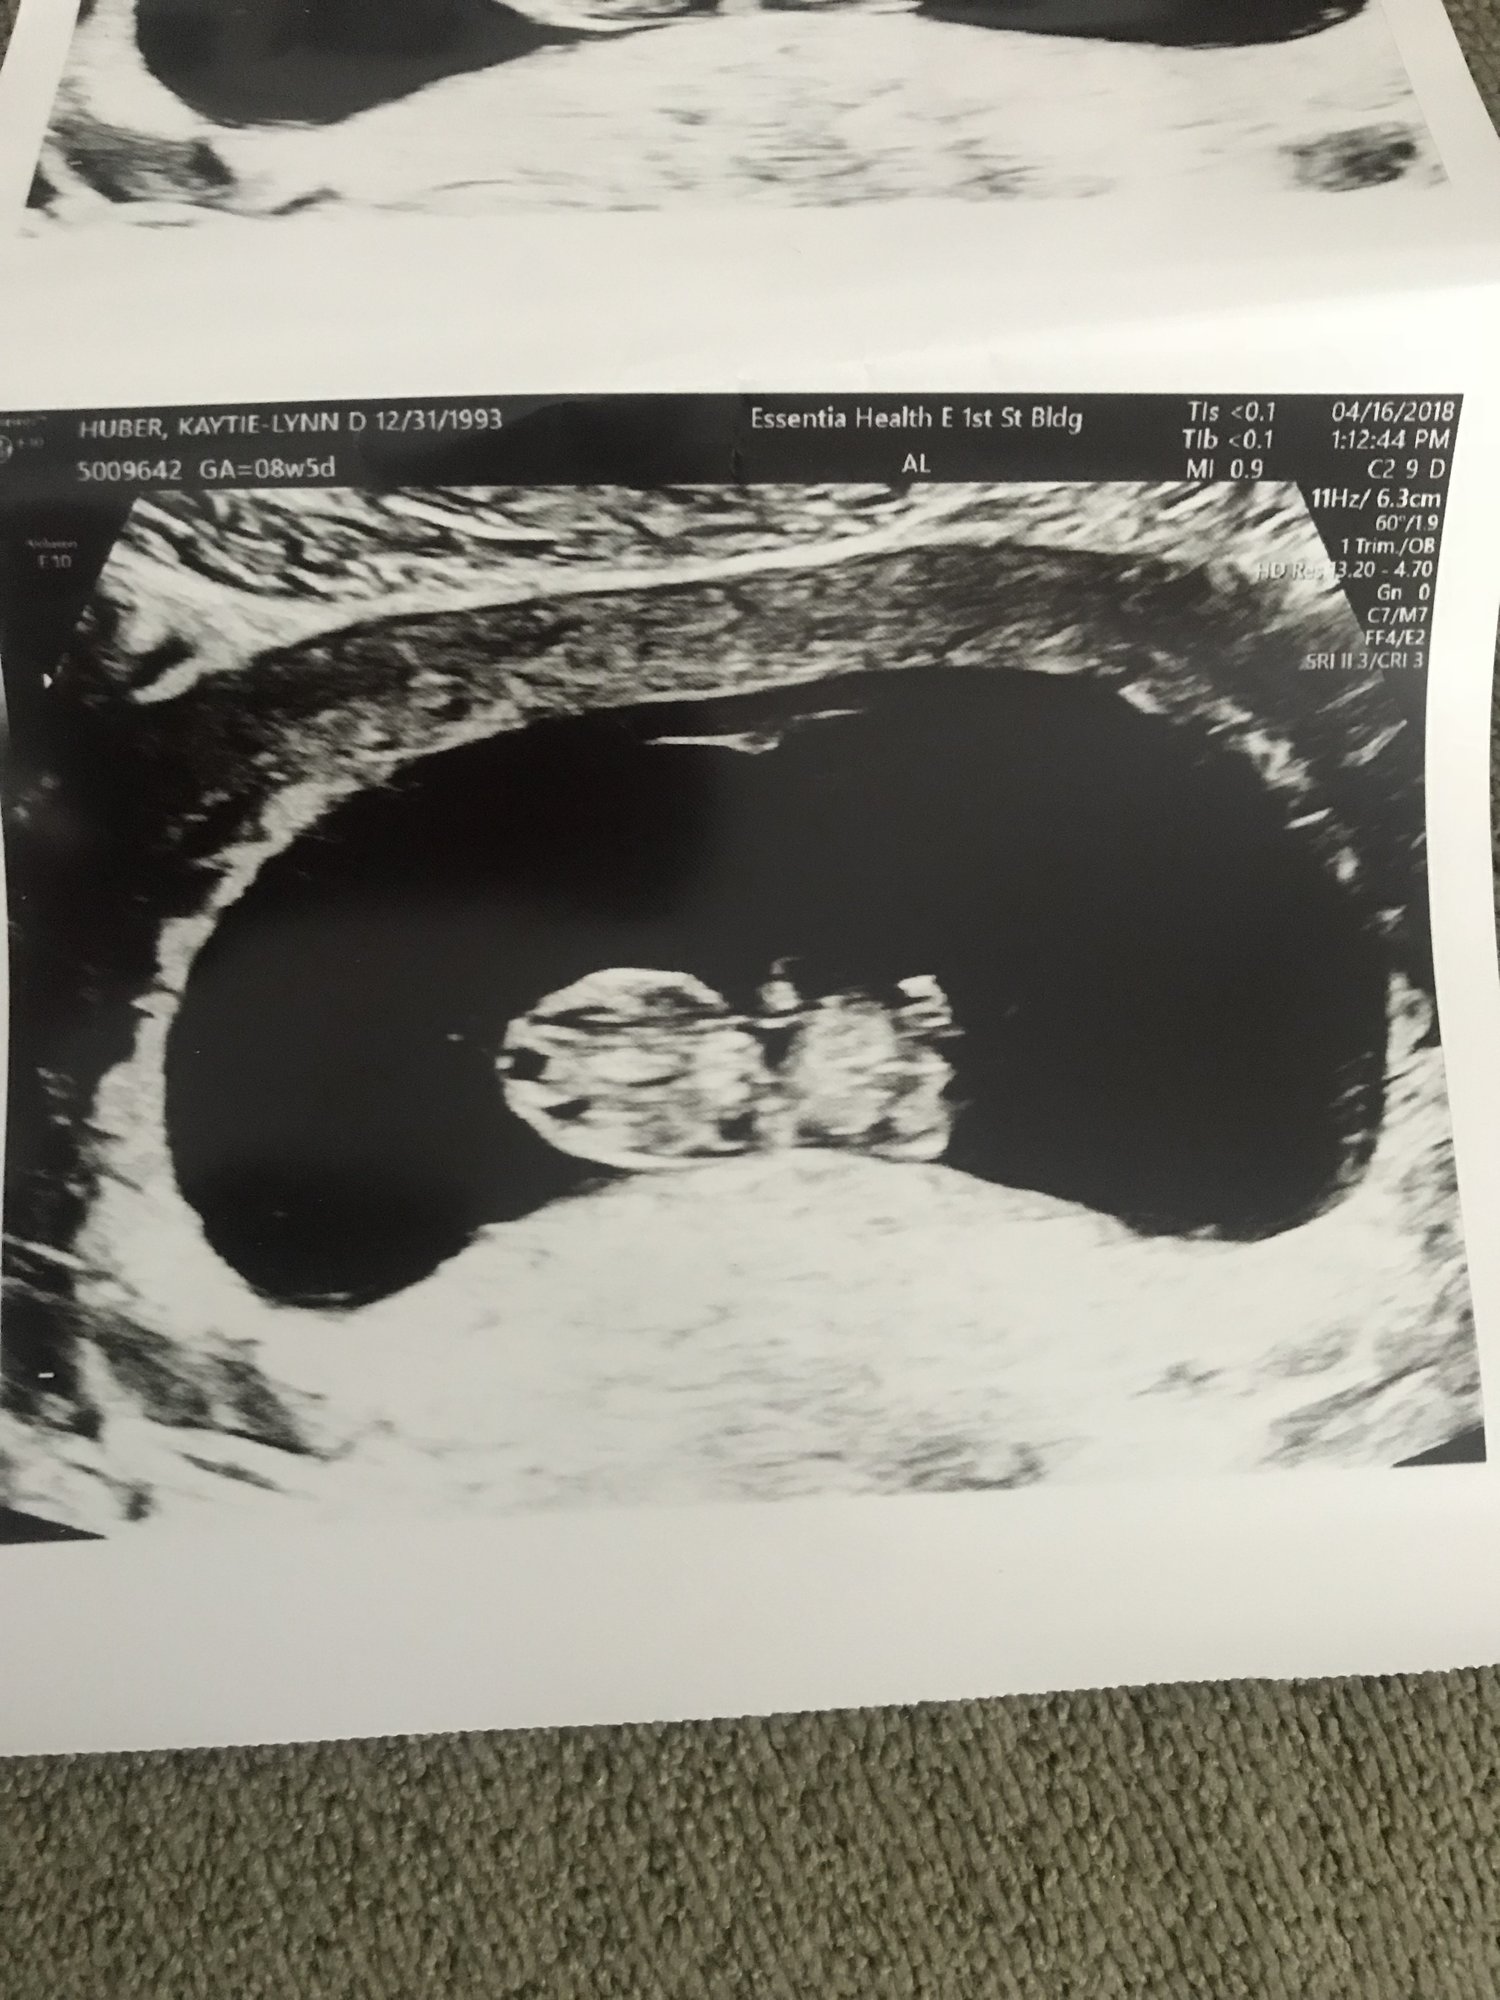

I'm 12w5d but measuring at 13w4d (!!!) I got to see my little bean bouncing around all over the place, and moving it's arms all over.

ETA picture since it didnt post the first time